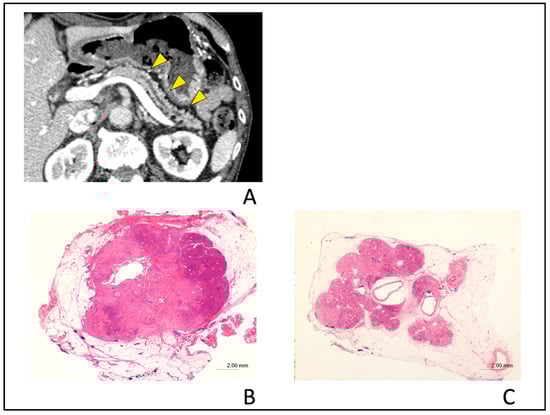

Figure 7.

Typical computed tomography (CT) images showing upstream pancreatic parenchymal atrophy in a 72-year-old man with stage IA (tumor diameter of 10 mm in size) pancreatic cancer. Localized main pancreatic duct dilation was detected in the pancreatic body in the CT after the recurrence of acute pancreatitis and tumor lesion was detected in endoscopic ultrasonography. (A); Typical CT images showing upstream pancreatic parenchymal atrophy (PPA). The area exhibiting PPA has an atrophic change in the whole upstream side of the lesion (yellow arrow heads). (B); Hematoxylin and eosin (H&E)-stained resected specimen shows cancer nodule with a diameter of 10 mm in size (H&E stain, ×0.5 magnification). (C); Severe atrophy of pancreatic parenchyma and fatty change were observed in the upstream section from cancer nodule (H&E stain, ×0.5 magnification).